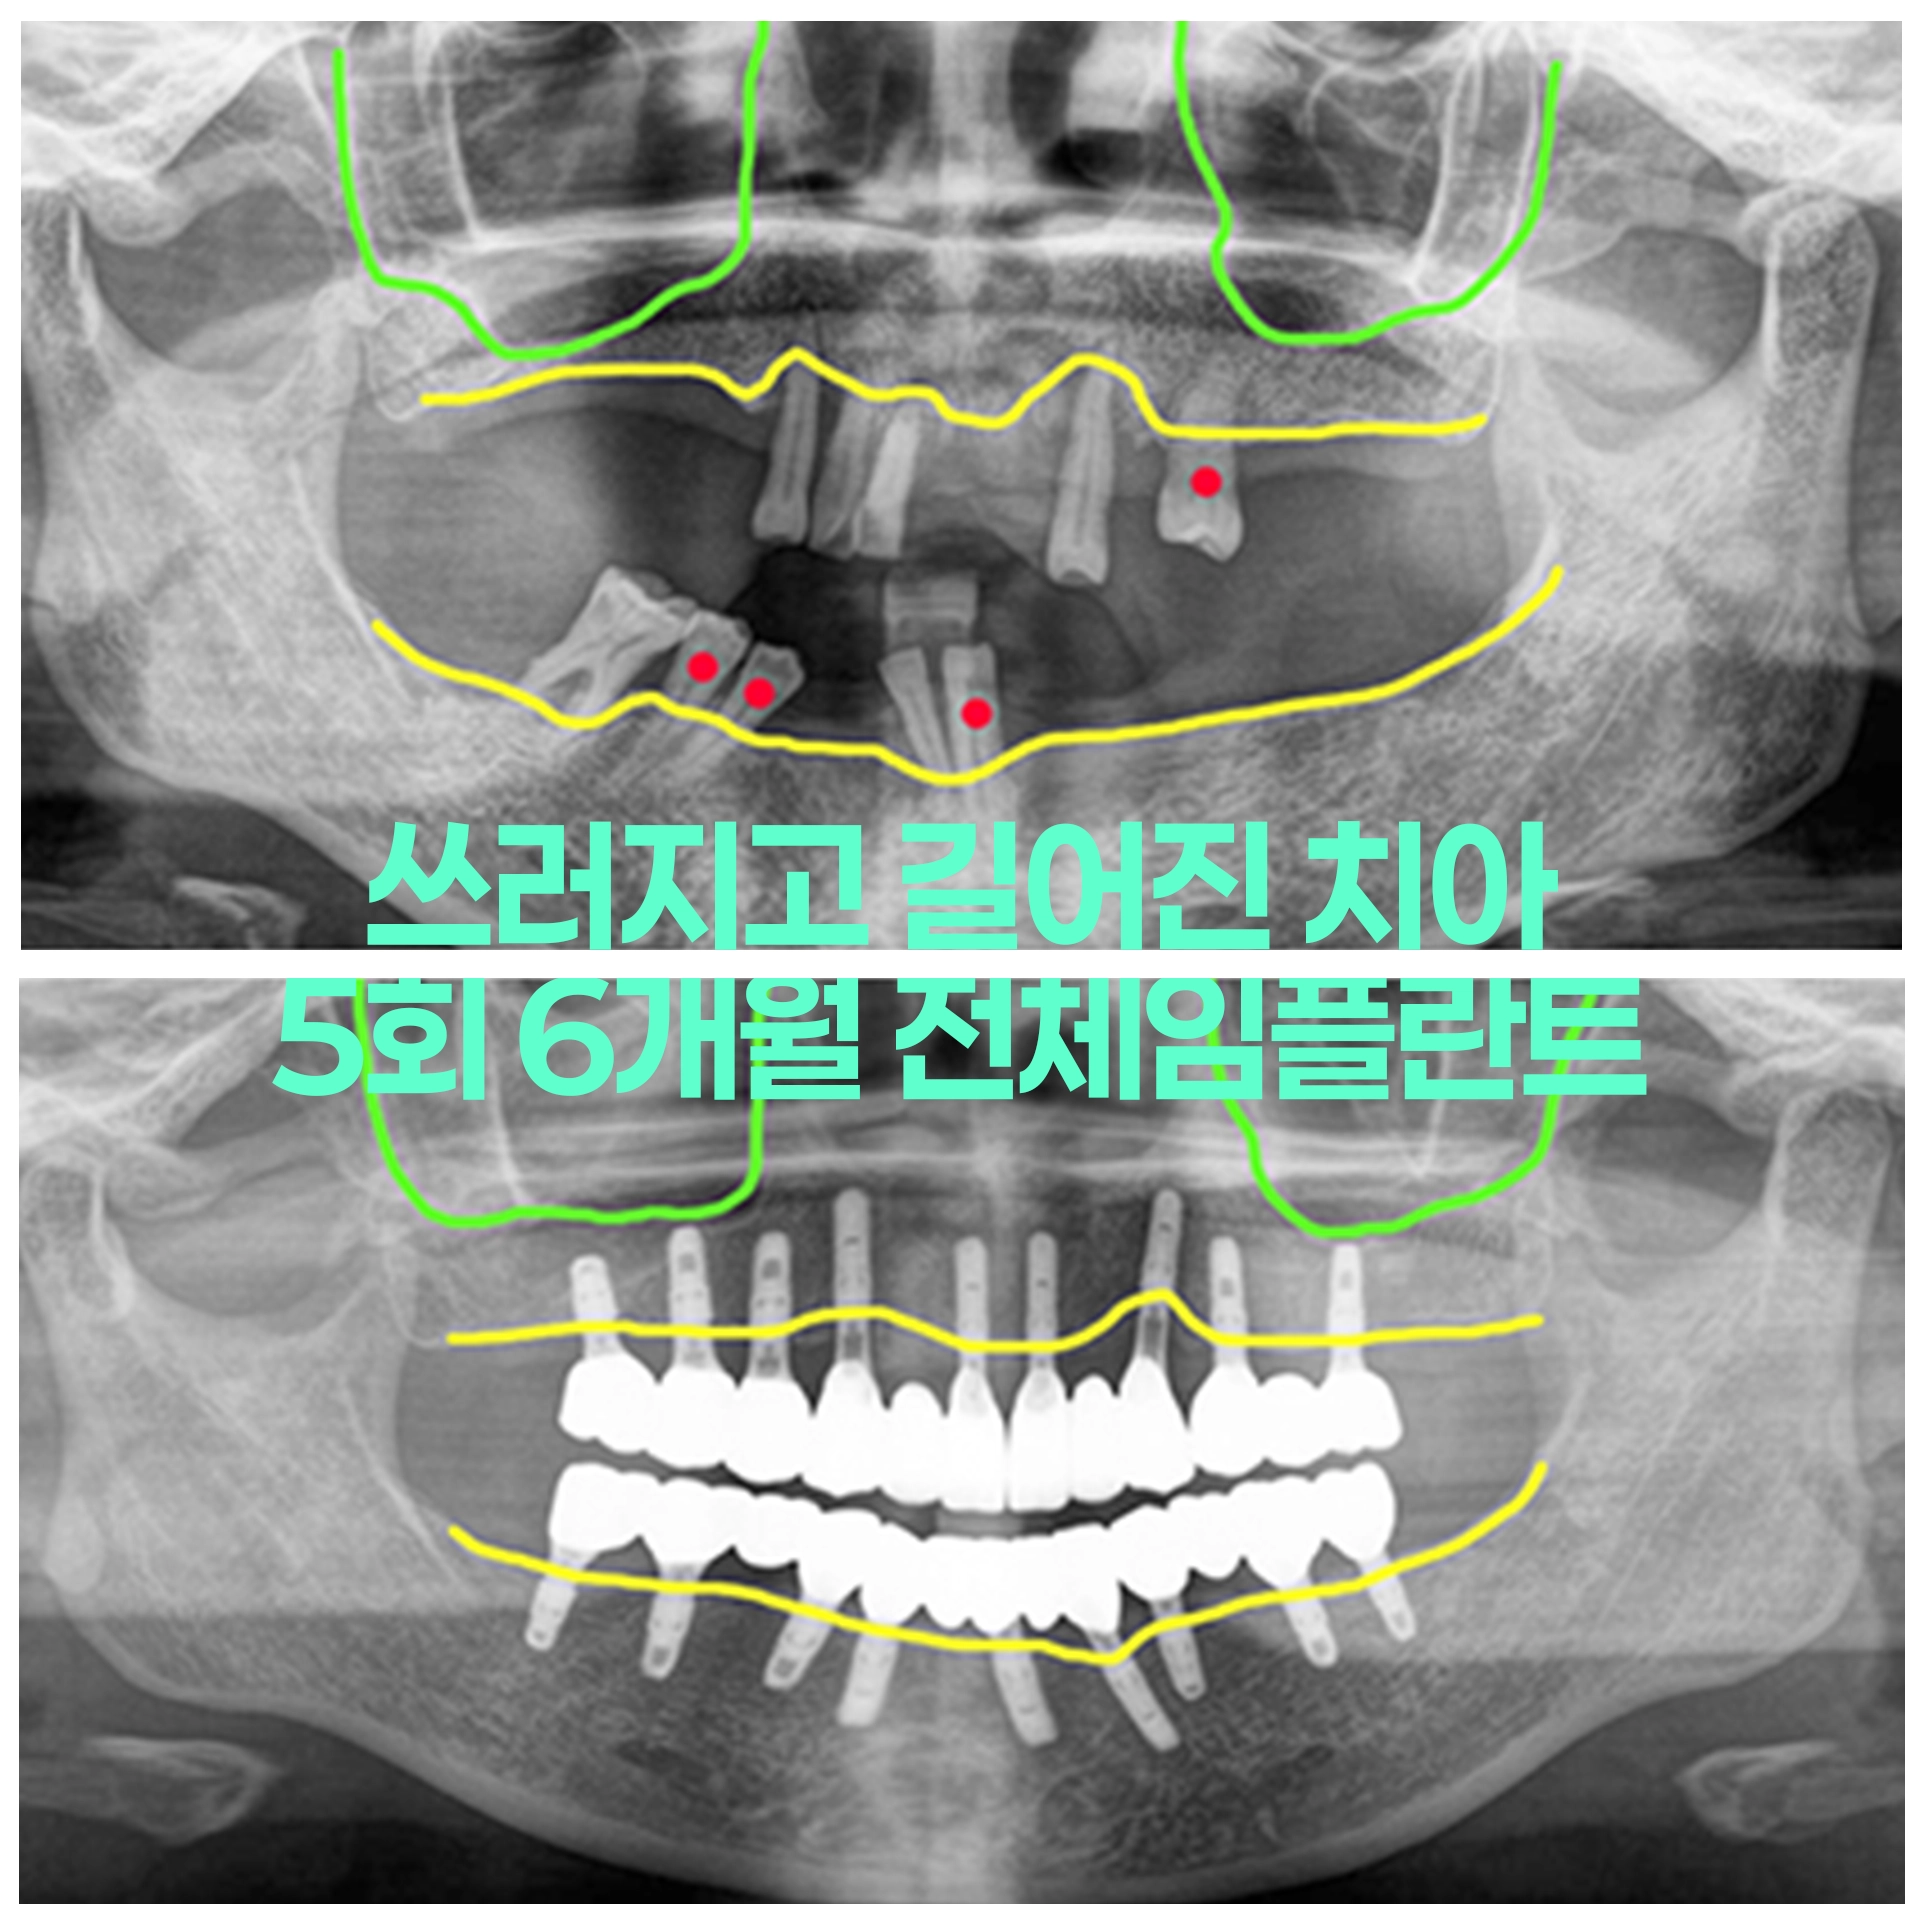

50대 남성 부분틀니 10년째 틀니 망가지고 치아 모두 흔들려 전체임플란트

50대 남성 치주염 방치해서 흔들리고 빠져 수술당일 임시치아 적용하는 즉시하중 전체임플란트